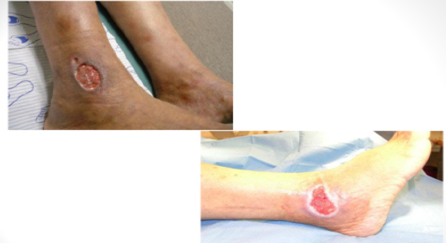

Ulkus pada tungkai adalah penyakit arteri, vena, kapiler dan pembuluh darah limfe yang dapat menyebabkan kelainan pada kulit,Ulkus kruris adalah luka terbuka disertai hilangnya epidermis dan sebagian atau seluruh dermis pada ekstrimitas bawah yang disebabkan oleh infeksi, gangguan pembuluh darah, atau keganasan.

Pembagian ulkus kruris dibagi ke dalam 4 golongan :

- Ulkus Tropikum.

- Ulkus Varikosum.

- Ulkus Arteriosum.

- Ulkus Neurotrofik.